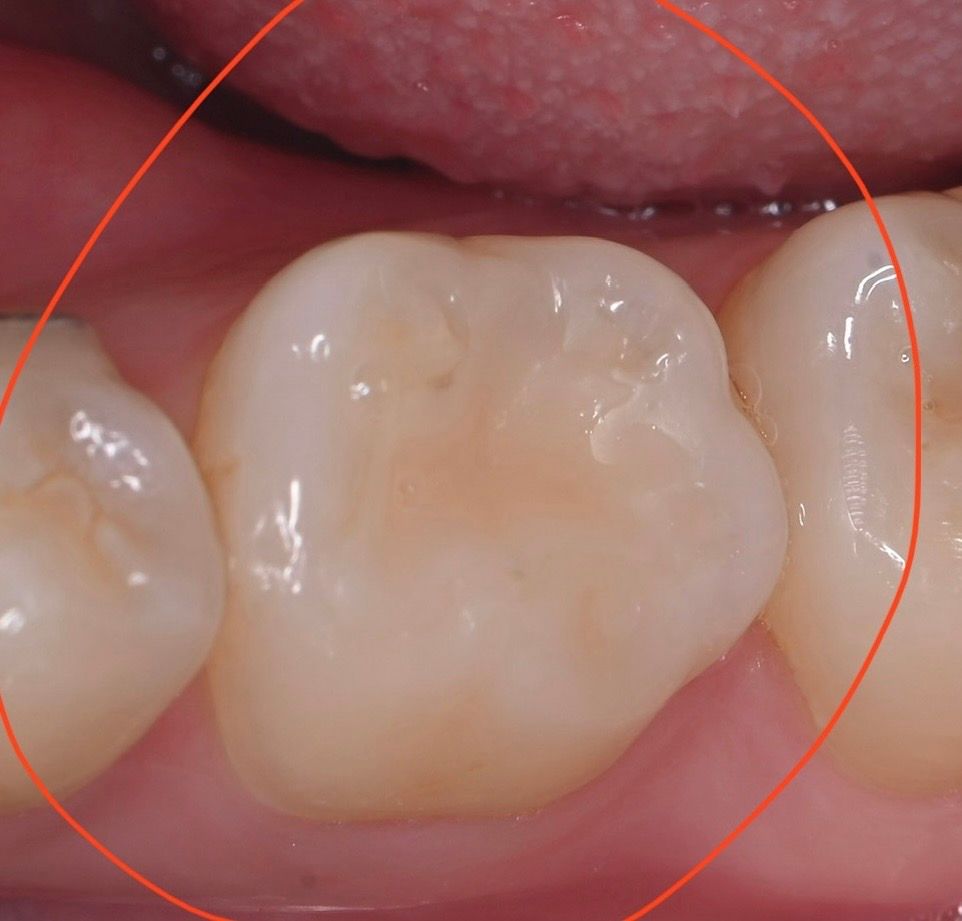

어금니 인레이 치료를 받았습니다 (아래 왼쪽 뒤에서 두번째 어금니)

1년동안 탈없이 잘 사용했는데 며칠전부터 자꾸 치아가 시립니다 가만히 있을때에도 은은하게 시리고 식사할때도 은은하게 시리는데 막 아프다 정도는 아닙니다

다만 잘못되었을까 걱정되네요 치아가 시리기전에 치과 검진을 갔었는데 (3주전) 그때는 별말씀 없으셨습니다.. 왜 시린건가요?.. 충치가생긴걸까요 아니면 인레이 틈이생긴걸까요?

컨디션이 안좋으면 며칠 일시적으로 그럴순 있습니다 일단 지켜보시고 증상이 심해지면 다시 치과 가보세요 지금 사진상으론 별다른 문제가 보이진 않습니다